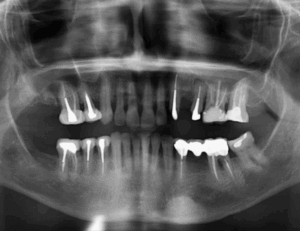

Paciente femenina de 51 años acude al Instituto para realizarse una tomografía volumétrica para rehabilitación oral, a la evaluación de la radiografía panorámica se observa

Paciente femenino de 69 años acude al Instituto para realizar una tomografía con fines de rehabilitación oral, a la evaluación de la radiografía panorámica se